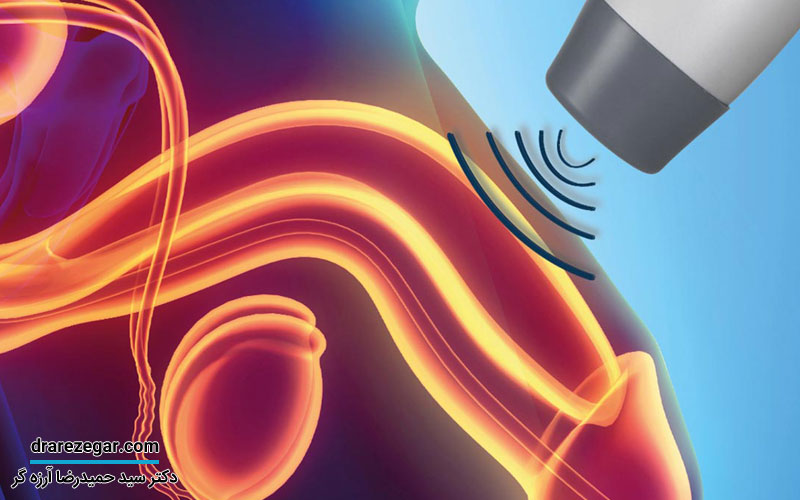

استفاده از پساری

یکی از روش های مطلوب برای درمان افتادگی مثانه استفاده از یک دستگاه سلیکونی به نام پساری است که می تواند داخل واژن قرار بگیرد و از مثانه و دیواره جلوی واژن حمایت کند. این وسیله در شکل ها و اندازه های مختلفی ساخته می شوند که برای جایگذاری آن نیازی به جراحی نیست و پزشک می تواند به راحتی در جای مناسب قرار دهد.